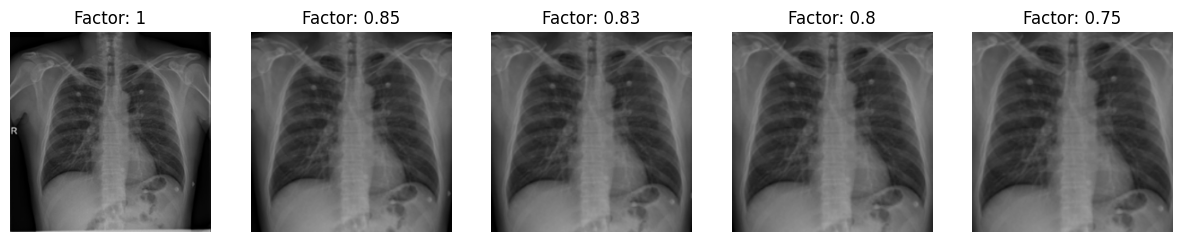

4. Zoom

Zoom

5. Zoom + CLAHE + Image Sharpening

Clip Size : 2, Grid Size: 15, Basic Sharpening Kernel, Zoom Factor : 0.83

Zoom + CLAHE + Sharpening

• Zoom (Factor of 0.83):

• Purpose: Crop out potential artifacts and noise along the image borders.

• Benefits: Standardizes the primary region of interest due to diverse radiological image presentations from various sources.

• Zooming: Effectively eliminates extraneous details, offering a clearer view of the primary chest region.